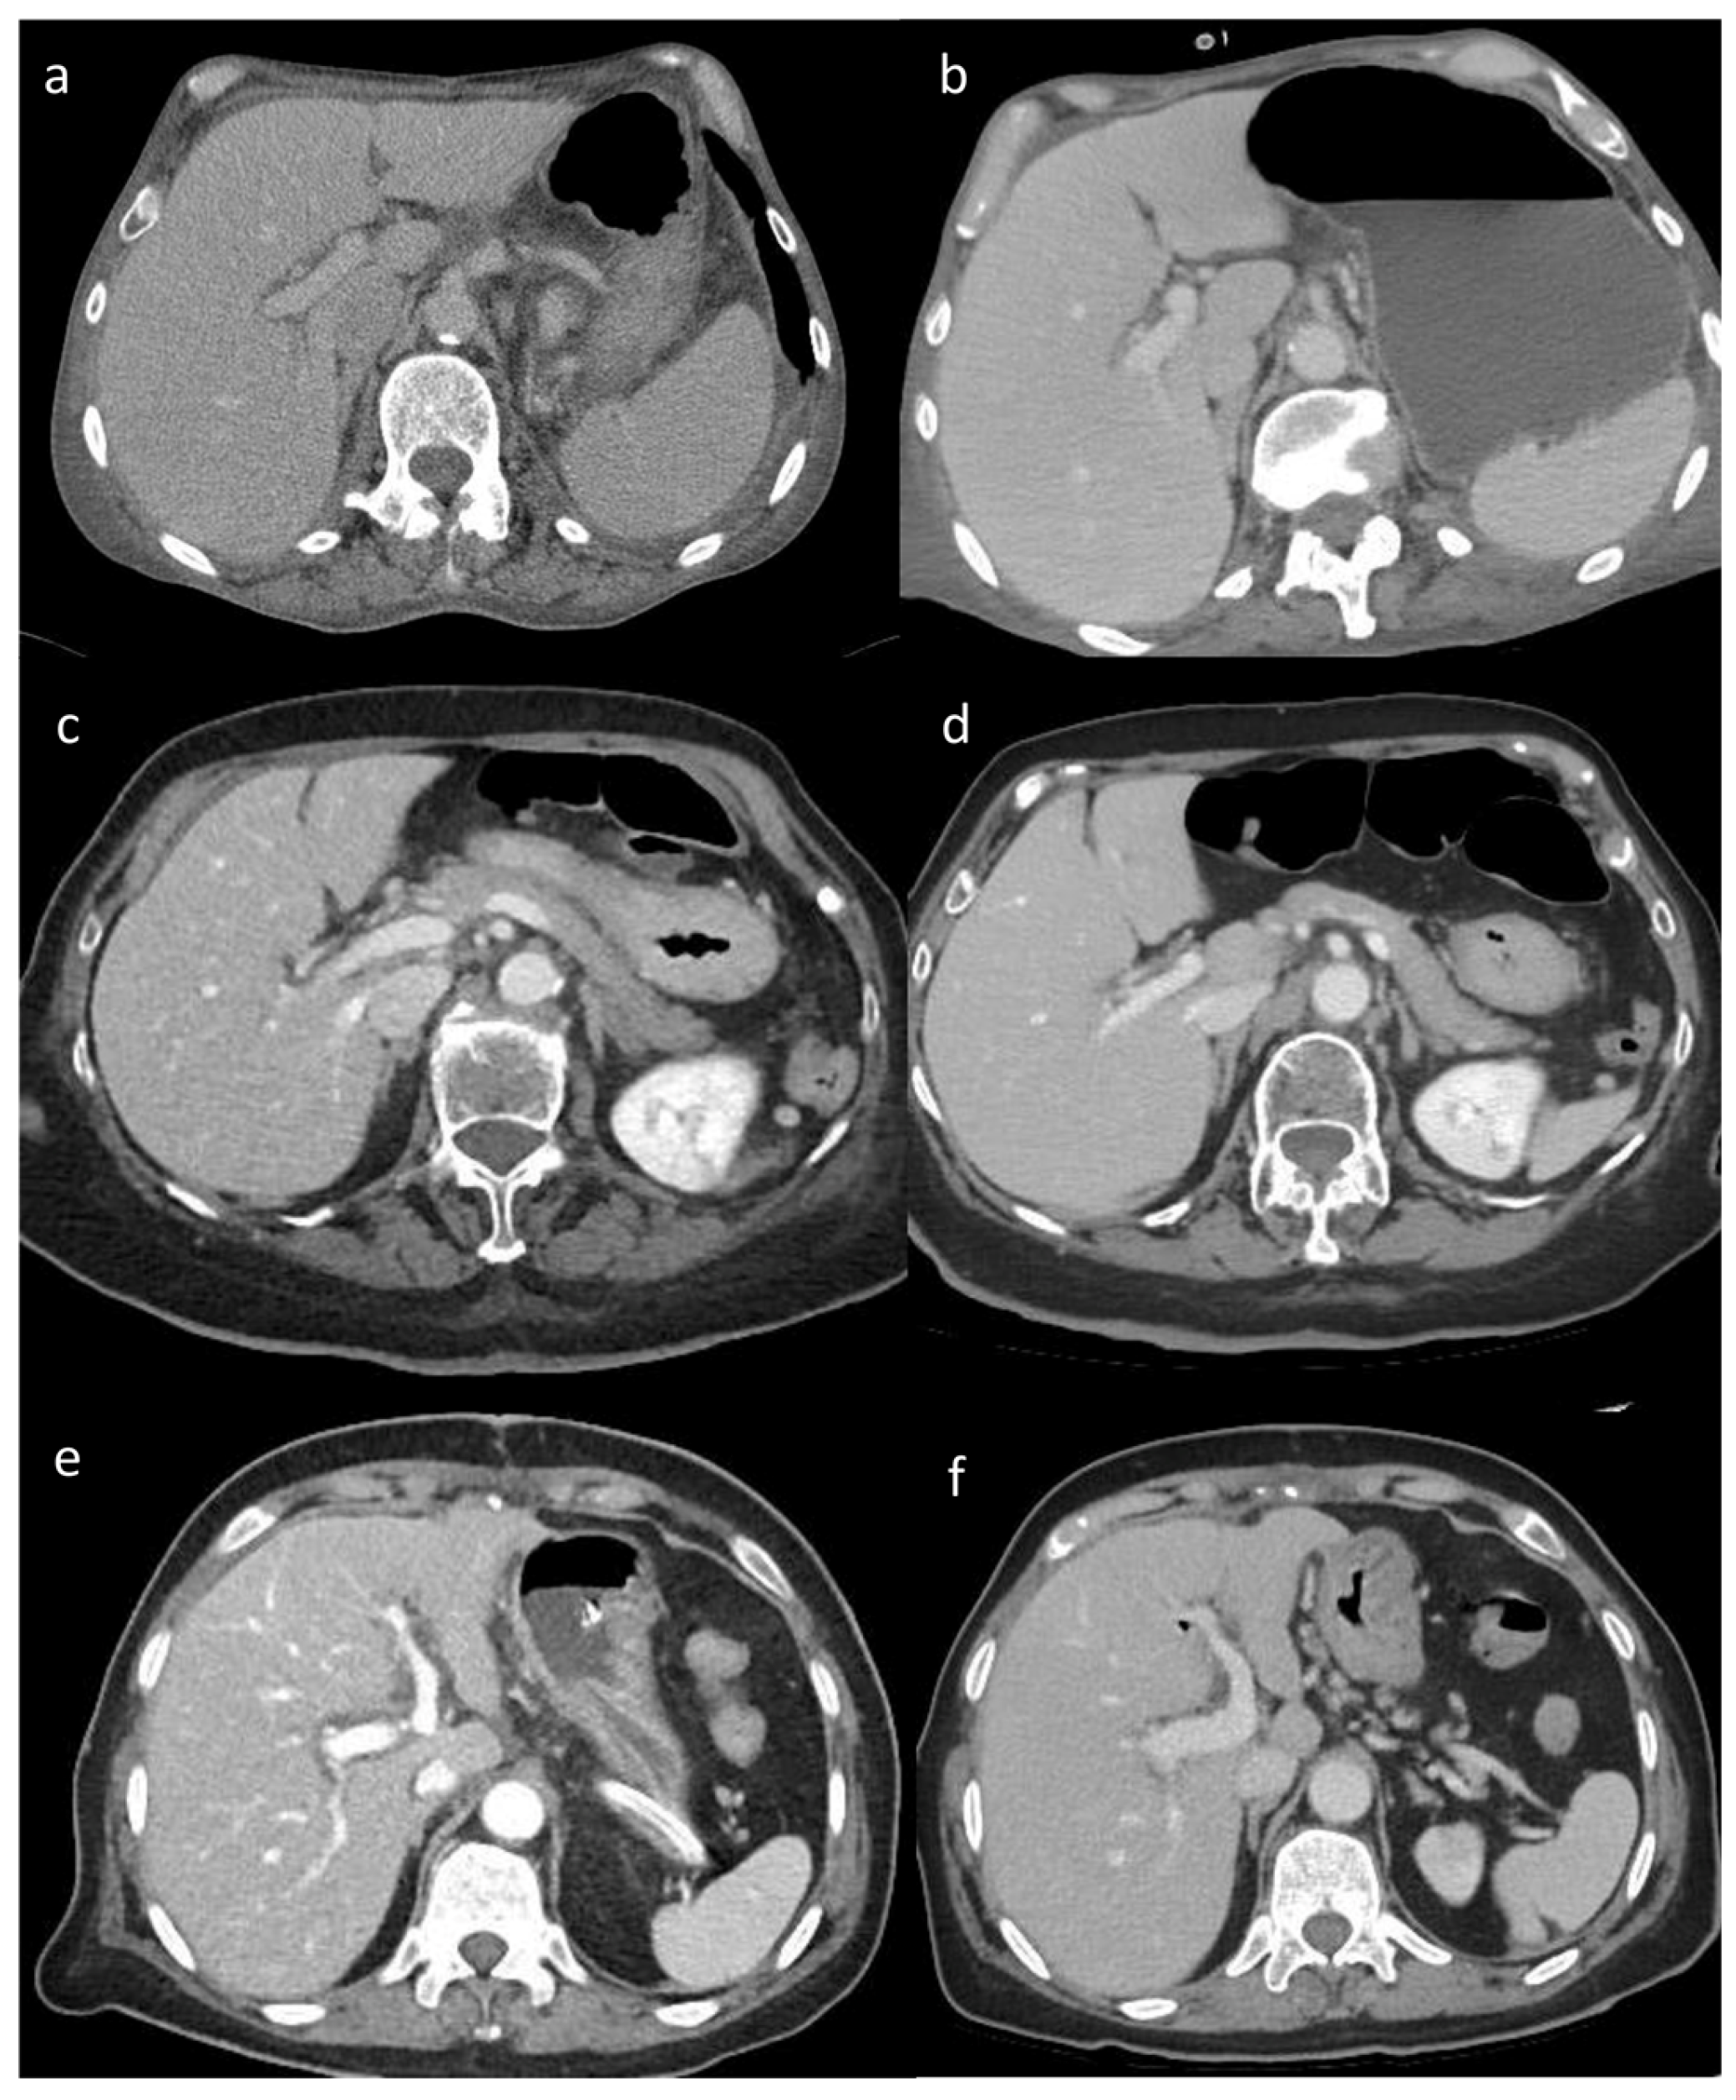

Figure 2. a - f. Visual analysis. Visual differences in abdominal parenchyma border definition and noise among different reconstruction algorithms (a, b) 45-year-old male patient after major surgery. (c, d) 47-year-old male patient after lung transplant. (e, f) 55-year-old male patient after cardiac transplant. Filtered Back Project (FBP) (a), Advanced Modeled Iterative Reconstruction model-based iterative reconstruction (ADMIRE) (c), and Adaptive Iterative Dose Reduction 3D (AIDR 3D) hybrid iterative reconstruction (e) vs. Deep Learning Image Reconstruction (DLIR) (b, d, f). FBP, ADMIRE, and AIDR 3D were scored as 2, 4, and 3, respectively, whereas DLIR images were scored as 5 by all reviewers.

Visual analysis results showed significant differences in the image quality of soft tissue among the three reconstruction methods (all p < 0.05). The image score of DLIR (mean score = 5) was higher than that of ADMIRE (mean score = 4) and AIDR 3D (mean score = 3) and FBP (mean score = 3) by 50% of observers. Both radiologists believed that DLIR had outstanding noise reduction. The subjective scores of the two radiologists were consistent (kappa value range: 0.48–0.91) (Figure 2).